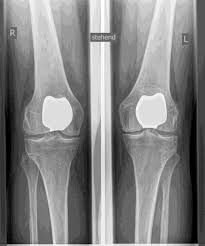

Las articulaciones artificiales de rodilla se denominan prótesis totales y prótesis parciales. Compruebo cuidadosamente de antemano qué prótesis es adecuada para usted basándose en el examen clínico, así como en base a radiografías o imágenes de resonancia magnética.

El reemplazo parcial de la articulación de la rodilla es posible en todas las áreas de la articulación, pero con mayor frecuencia se realiza en el interior de la articulación de la rodilla y, a menudo, se denomina coloquialmente prótesis de trineo. Al igual que en la dentadura postiza completa, el cartílago defectuoso se reemplaza con una nueva superficie y se inserta una incrustación de plástico en el medio. Para una prótesis parcial, todas las estructuras ligamentosas, especialmente los ligamentos cruzados, deben estar prácticamente intactas.